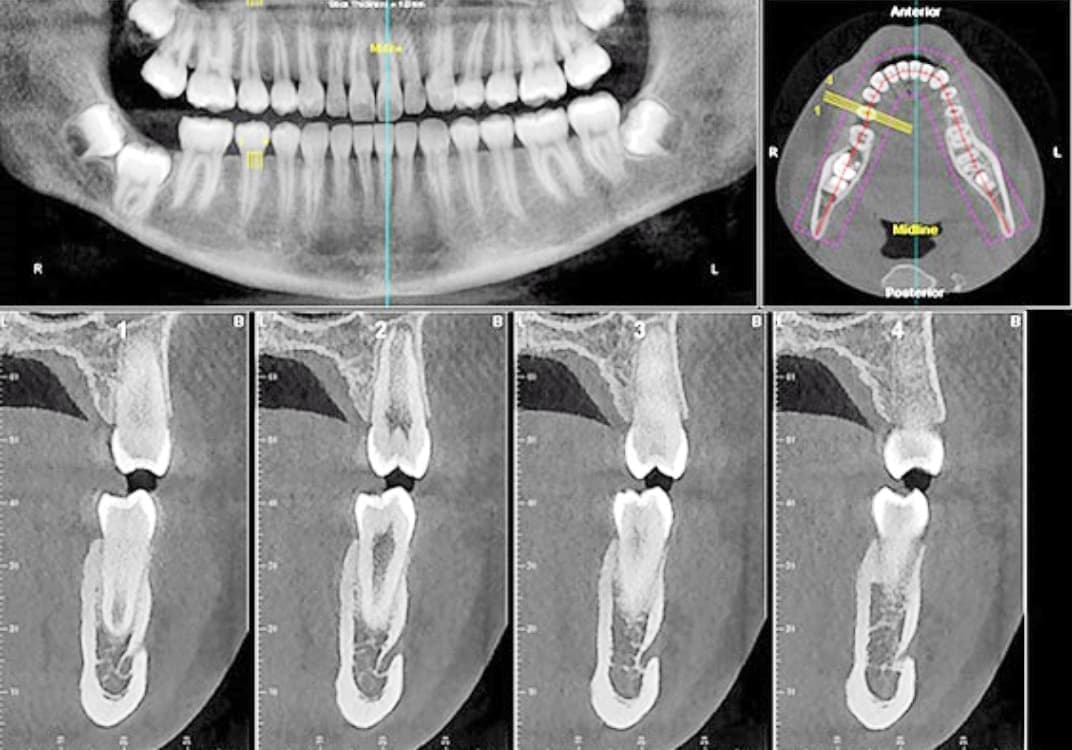

当院では、歯科用CT3Dデジタルレントゲンを活用し、身体への負担を少なく、状況を詳しく把握し、的確な治療を提供出来るよう心掛けております。

CTデジタルレントゲンに使われているX線センサーは高感度で照射時間も短く、より低線量でのレントゲン画像の取得が可能となり、お子様にも安心です。

インプラント手術や歯周病治療、歯の根の病気に関係する治療の正確な診断、治療計画には、CTによる撮影が欠かせません。

例えば、親知らずの抜歯や骨内に埋伏している過剰歯の抜歯等、正確な位置や神経や血管等との距離を3次元的に把握することで負担の少ない安心な処置が行えます。